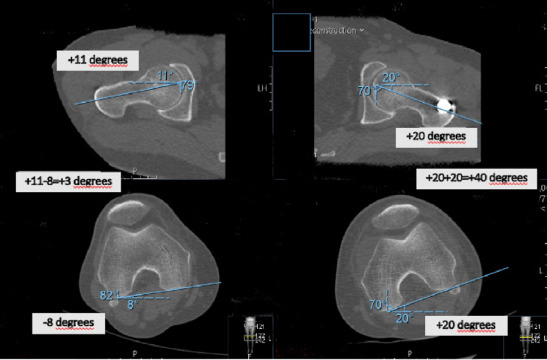

Methods: A retrospective cohort study was conducted involving 54 adults treated with closed static-locked IMN for diaphyseal femur fractures between 2014 and 2019. Rotational alignment was assessed using computed tomography (CT)-measured femoral anteversion (FAV) differences, with a threshold of ≥15° defined as malalignment. Multivariate logistic regression was employed to examine associations with fracture pattern, nail entry site, surgical timing (day vs. night), and coronal alignment. Functional outcomes were assessed using the WOMAC (Western Ontario and McMaster Universities Osteoarthritis Index) knee, Harris hip, Lower Extremity Functional Scale, and Kujala patellofemoral scores. Receiver operating characteristic (ROC) analysis was used to determine optimal FAV thresholds.

Results: Rotational malalignment (≥15° FAV difference) was observed in 33.3% of cases, with 94.4% involving internal rotation. Multivariate analysis identified no independent predictors among the following factors: fracture location (proximal 44.4% vs. middle 29.2%, p=0.625), AO classification (Type A 34.3% vs. Type C 33.3%, p=0.914), nail entry site (lateral trochanteric 40% vs. piriformis 16.6%, *p*=0.574), and surgical timing (night 26.1% vs. day 38.7%, p=0.228). Patients with malalignment demonstrated significantly poorer functional outcomes, as evidenced by higher WOMAC knee scores (12.7+-4.8 vs. 6.4+-4.8, p<0.001). ROC curve analysis identified 13.5° as the optimal FAV threshold (area under the curve, AUC: 0.78), although the 15° cutoff maintained strong clinical utility with a specificity of 83%.